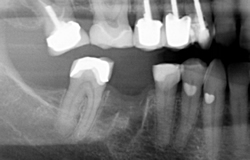

Before/After Example